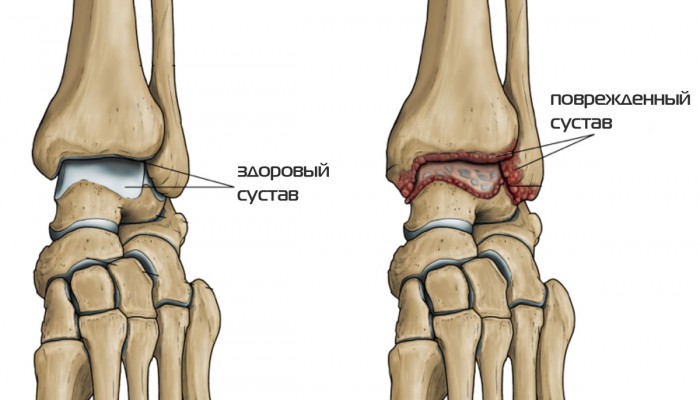

Деформирующий остеоартроз голеностопного сустава (ДОА) – тяжёлое заболевание, приводящее к инвалидности, если вовремя не начать лечение. Начальная стадия всегда протекает бессимптомно. ДОА характеризуется разрушением хряща (дегенеративные изменения), воспалением суставной капсулы, разрастанием остеофитов, ослаблением связочного аппарата.

Существуют определённые общие симптомы, характеризующие заболевание. Это первоначальный болевой синдром. Он появляется после довольно большой нагрузки на сустав и не воспринимается иначе, как обычное переутомление. Хруст, щёлканье, скрип в голеностопе – первый звоночек при деформирующем остеоартрозе.

Остеоартроз голеностопа — это дегенеративное заболевание суставов, характеризующееся износом хрящевой ткани, что приводит к боли, ограничению подвижности и изменению структуры сустава. Он может развиваться в результате травм, возрастных изменений, избыточного веса или наследственных факторов, и проявляется симптомами, такими как боль при движении, отечность и хруст в суставе. Лечение может включать физическую терапию, медикаменты и в некоторых случаях хирургическое вмешательство.